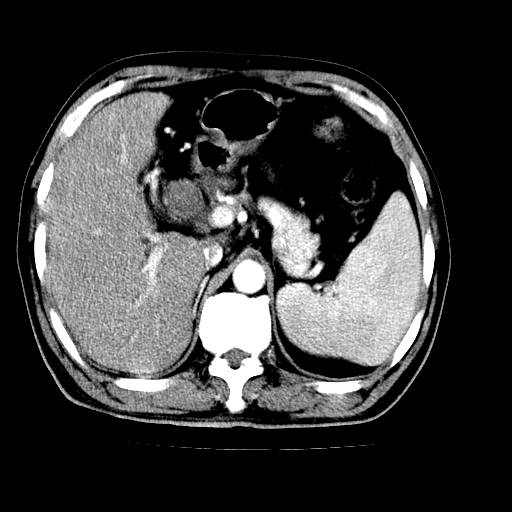

男,66岁,上腹部不适、黄染一周。彩超示:肝左叶占位,肝内胆管扩张,胆总管扩张,胆总管占位?

肝左叶不规则软组织肿块影,边缘不规整邻近肝实质受累分界不清;肝内胆管(左叶)明显扩张成“软藤状”,诊断:肝左叶胆管细胞癌。

肝左叶占位性病变,并胆管扩张,符合胆管细胞癌ct表现,门脉左支受累,左肾囊肿。窗宽太窄了,其他的看不清

左叶胆管细胞癌累及胆总管,门脉左支受侵,慢性胆囊炎胆结石,左肾小囊肿

支持肝左叶肝内胆管细胞癌伴胆总管及门脉左支受侵。

肝左叶不规则软组织肿块影,边缘不规整邻近肝实质受累分界不清;肝内胆管(左叶)明显扩张成“软藤状”,诊断:肝左叶胆管细胞癌。胆囊钙乳症。